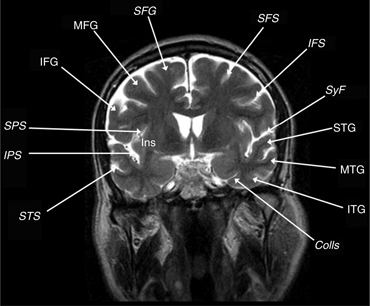

Cranial computed tomography (CT) has utility in presenting bone detail and the presence of calcification within a tumor bed. However, the anatomic detail provided by magnetic resonance imaging (MRI) is exquisite and provides cortical anatomical landmarks that are useful in preoperative planning. Relatively predictable patterns of sulci and gyri allow for identification of the primary sensory/motor cortices and speech centers. The concordance between MRI images and gross anatomical specimens has revealed “keys” for cortical landmark identification (4, 5). The first key is the Sylvian fissure and its five major rami. The posterior horizontal ramus (PHR) forms the main fissure that is visible on the convexity of the brain; it extends rostrally into the posterior ascending (PAR) and descending rami (PDR). The PAR is “capped” by the supramarginal gyrus (SMG). Anteriorly along the PHR, the sylvian fissure extends into two sulci, the anterior horizontal and anterior ascending rami. These rami extend into the inferior frontal gyrus (IFG) dividing it into the pars orbitalis, pars triangularis, and pars opercularis. The pars triangularis (Brodmann’s areas 45) and pars opercularis (Brodmann’s area 44) represent the primary motor or expressive speech area (Broca’s area).

The frontal lobe contains three gyri (superior, middle, inferior) separated by the superior and inferior frontal sulci. The superior frontal gyrus is appreciated on both axial and sagittal images (Figure 1). The middle frontal gyrus (MFG) extends posteriorly and fuses with the vertically oriented precentral gyrus. The precentral sulcus starts at midline and extends anteriorly and laterally in an oblique direction. The next key finding is the merging of the inferior frontal sulcus with the inferior ramus of the precentral sulcus, forming a “T” shape (4, 5). More posteriorly, the central sulcus is identified over the convexity on axial or sagittal images. It is oriented obliquely from posterior to anterior and does not extend all the way into the Sylvian fissure. Inferiorly, the precentral gyrus and postcentral gyrus merge under the central sulcus through a “U”-shaped gyrus (the subcentral gyrus). The post-central gyrus is characteristically narrower than the precentral gyrus (4, 5). Posteriorly, the Sylvian fissure is capped by the SMG, which is the anterior most portion of the inferior parietal lobule. Inferiorly, within the temporal lobe, coursing in parallel with the Sylvian fissure, is the superior temporal sulcus, which is capped posteriorly by the angular gyrus, the posterior limit of the inferior parietal lobule. The angular gyrus (Brodmann’s area 39) and posterior aspect of the superior temporal gyrus (STG) (Brodmann’s area 22) represent the primary receptive speech area (Wernicke’s area). The SMG (Brodmann’s area 40) contains fibers from the arcuate fasciculus that connect Wernicke’s and Broca’s areas (4, 5). The cingulate sulcus separates the cingulate gyrus from the medial aspect of the superior frontal gyrus. If followed posteriorly, the cingulate sulcus angles superiorly to form the pars marginalis, marking the posterior aspect of the paracentral lobule. The paracentral lobule houses the central sulcus, Broadman Areas 3,1,2 and 4,6. On axial images, the pars marginalis may be appreciated as a “bracket” (pars bracket) extending symmetrically from midline left and right. Anterior to this are the primary motor cortex and the postcentral sulcus. Areas 3,1,2 relate to the primary sensory cortex, and areas 4,6 include primary motor and supplemental motor areas (4, 5) (Figures 1 and 2).

Eloquent cortex generally implies speech, sensorimotor, and visual areas. Broca’s area lies in the pars opercularis and triangularis of the IFG Brodman’s area 44 (Figure 3). It controls the complex orofacial movements required to articulate speech and lies just anterior to motor cortex for lip, tongue, face, and larynx movements. Additional essential language sites in the dominant hemisphere can extend into the MFG, STG, middle temporal gyrus (MTG), or the insula. Expressive aphasia results from injury to Broca’s area, while receptive aphasia results from injury to Wernicke’s area (Figure 3). Injury to the arcuate facsiculus or white matter tracts connecting these speech areas results in conduction aphasias with impaired repetition. Injury to association cortex around the speech areas results in transcortical aphasias in which the primary function is impaired but repetition is preserved. The fusiform gyrus may also participate in speech, “basal temporal language area,” although deficits from surgical resections in this area typically recover. Auditory functions are bilaterally represented and resections involving the transverse temporal gyri in one hemisphere are well tolerated. Optic radiations, representing the inferior half of the contralateral retina, loop forward over the temporal horn before arching back toward the striate cortex in the banks of the calcarine fissure. Temporal resections that encroach upon these fibers cause a contralateral upper outer quadrantonopsia, a “pie-in-the-sky” defect, which is also well tolerated (3, 1821).

Fig 3

Figure 3 Lateral sagittal T1-weighted MRI scans. Pars triangularis (Pars Tr), pars opercularis (Pars Op), posterior horizontal ramus of the sylvian fissure (PHR), and supramarginal gyrus (SMG). Subcentral gyrus (SCG), precentral gyrus (PCG), central sulcus (CS), postcentral gyrus (PoCG), supramarginal gyrus (SMG), angular gyrus (AG), and superior temporal sulcus (STS).